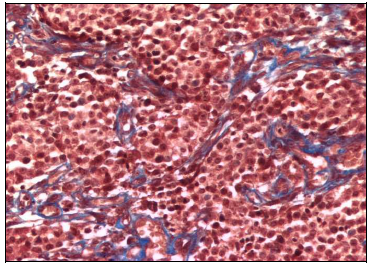

Tissue section of CTVT from day 0, before thalidomide treatment, revealed tumor features characteristics of the progressive phase of tumor growth. There was a prevalence of big, round or polyedric tumoral cells, with well defined nuclei and prominent nucleoli in a central or eccentric location. Mitotic figures were also frequently observed. CTVT cells were arranged in groups surrounded by few and thin collagen type I fibers (Figure 3). Small and occasional areas of perivascular infiltration by lymphocytes was observed.

Figure 3 CTVT tissue section from day 0 previous to thalidomide treatment. Scarce and thin collagen type I fibers staining blue surrounding numerous tumoral cells. Masson Stain (200X).